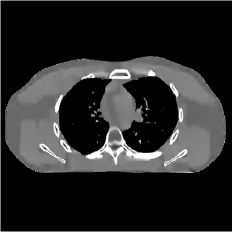

Fig. 2 shows representative reconstructions for FBP, PWLS-EP, PWLS-ST, and PWLS-MRST2. Compared to FBP and PWLS-EP, PWLS-MRST2 significantly improves image quality by reducing noise and preserving structural details. Furthermore, PWLS-MRST2 improves the quality of the central region and image edges compared to PWLS-ST.

| (a) FBP | (b) PWLS-EP | (c) PWLS-ST | (d) PWLS-MRST2 |